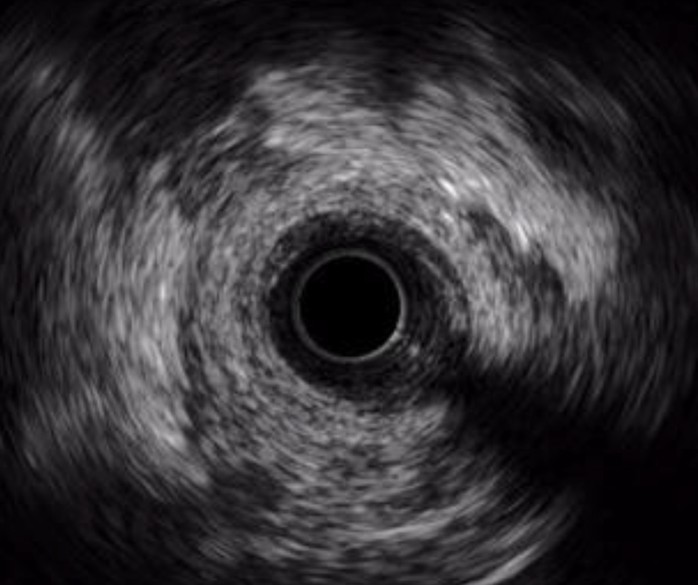

High-Definition IVUS image quality helps physicians more accurately identify lesion length, assess plaque morphology, and determine the tools required for vessel prep. See how OPTICROSS HD’s 60 MHz images stack up against the competition.

OPTICROSS HD Imaging Catheter 60MHz

IVUS image of inside a coronary vessel using the 60MHz Opticross catheter

Axial resolution: 22µm